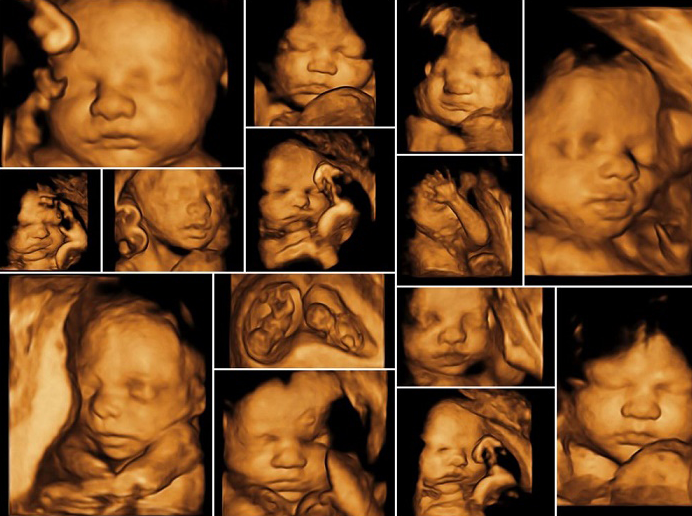

Siêu âm 3D là gì? Đó là một trong các công nghệ siêu âm đang phát triển hiện nay. Siêu âm 3D là công nghệ siêu âm 3 chiều, có thể ghi lại các hình ảnh ở nhiều góc độ khác nhau. Những hình ảnh thu được từ siêu âm 3D rất sắc nét, cho phép thấy được cả những chi tiết nhỏ nhất của thai nhi.

Mẹ nên siêu âm 3D vào tuần thứ 26 - 30 của thai kỳ thì hình ảnh thai nhi rõ nét và chính xác nhất. Trong khoảng thời gian này, chất béo ở dưới da của thai nhi tạo thành khuôn mặt của thai nhi rõ nét hơn. Nếu siêu âm vào những thời điểm khác thì vị trí của thai nhi hoặc những thay đổi của cơ thể thai nhi không phù hợp để cho ra được những hình ảnh toàn diện nhất.

Hình ảnh siêu âm 3D vào những thời điểm khác nhau sẽ cung cấp những thông tin khác nhau, cụ thể:

Hình ảnh siêu âm 3D ở tuần thứ 14 - 18 cho phép mẹ nhìn thấy toàn bộ cơ thể của em bé trong một bức ảnh. Trong giai đoạn này của thai kỳ, em bé rất năng động, mẹ có thể quan sát được tất cả các cử động của thai nhi như đá chân, vẫy tay, nắm chân,...

Khi siêu âm 3D, mẹ nhận ra bé có hai mắt, mũi và miệng nhưng không nhìn thấy chi tiết bố cục khuôn mặt.

Các đặc điểm trên khuôn mặt bé hiển thị rõ ràng hơn. Do đó, bác sĩ thường khuyên mẹ nên siêu âm trong giai đoạn tuần 19 - 26 của thai kỳ nếu đang mang thai song sinh.

Trong tuần thứ 27 - 40, em bé thường cúi đầu khi siêu âm. Đây là thời gian thích hợp để có được những bức ảnh chi tiết cận cảnh khuôn mặt của em bé.